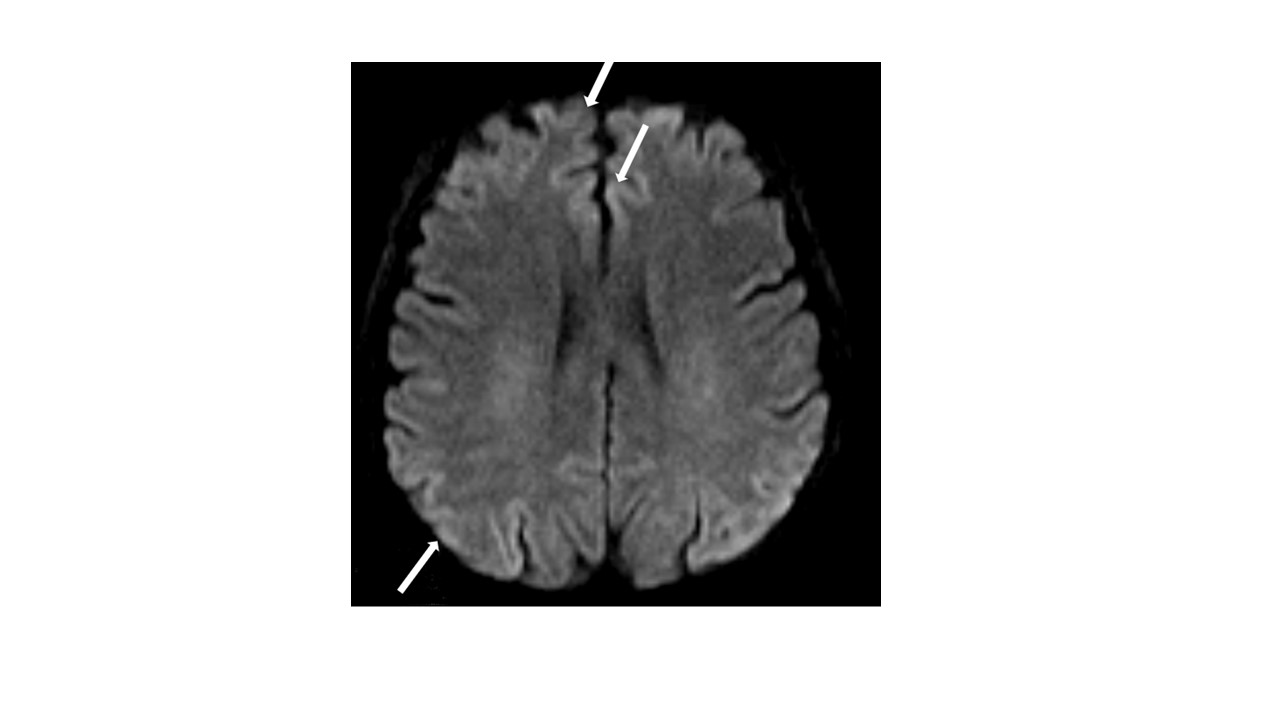

Case Presentation: A 54 -year-old female patient was admitted to intensive care unit (ICU) after a living donor liver transplantation (LDLT) at early postoperative period. Her medical history had diabetes mellitus, cryptogenic cirrhosis, portal vein thrombosis, hepatorenal syndrome, and recurrent hepatic encephalopathy episodes and TIPS. Her MELD and Child Pugg scores were 19 and 11C, respectively. At ICU admission APACHE-II score was 8, she was intubated and needed cardiovascular support with vasopressors and inotropes. A total of 24 sessions of therapeutic plasma exchange were applied for delayed graft response due to small for size syndrome and continous renal replacement therapy (CRRT) was applied due to stage 3 acute kidney injury. On the 8th day of invasive mechanical ventilation, 48 hours after sedation weaning, there was no awareness and GCS was 8. Cerebral MRI DWI showed a ribbon-like signal hyperintensity of cerebral cortical gyri (cortical ribboning) of the right predominant bilateral frontal, parietal, and occipital lobes, known as the cortical ribbon sign (Figure-1). Lumbar puncture could not be performed due to thrombocytopenia and EEG could not be performed due to hemodynamic instability. CJD was not considered in the patient because she had no history of prion exposure and her conscious improved without CJD treatment on 10th day of ICU. Therefore, it was considered that the patient had hepatic encephalopathy due to her current metabolic state. The patient died on the 14th day of ICU admission due to sepsis related to multidrug-resistant bacterial infection and respiratory syncytial virus.